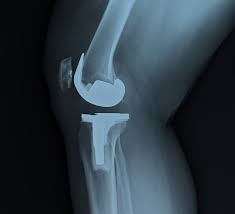

¿En qué consiste la cirugía de prótesis total de rodilla?

La prótesis total de rodilla es un procedimiento en el que se reemplazan las superficies dañadas de la articulación por componentes metálicos y de polietileno de alta durabilidad.

La cirugía elimina el desgaste causado por artrosis avanzada y permite recuperar movilidad y aliviar el dolor.

Se retira el cartílago y hueso deteriorado.

Se colocan componentes que recrean la forma natural de la rodilla.

Se equilibran los ligamentos para brindar estabilidad y movimiento fluido.